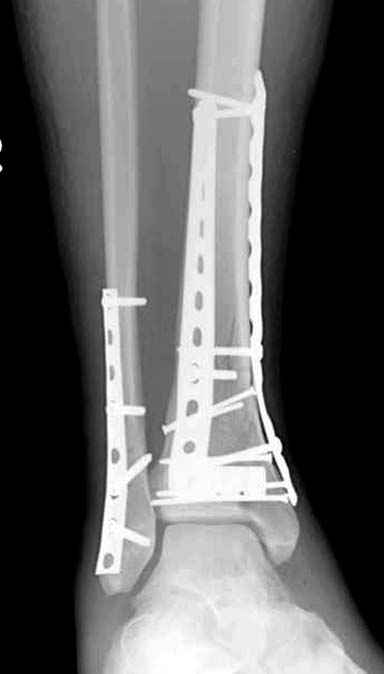

Спасибо за советы. Выполнен МОС обоих костей голени

По представленным послеоперационным снимкам создаётся впечатление сохраняющегося подвывиха + итраоперационно обнаруженный разрыв межкостной мембраны.

Извините за некачественные снимки и неправильную укладку в прямой проэкции. Подвывих рентгенологически не определяется. Кроме этого, после МОС малоберцовой кости интраоперационно однозубым крючком проверена стабильность синдесмоза - он стабилен. Кроме этого, интраоперационно проверена стабильность стопы в голеностопе - люфта ее при боковых отклонениях не определяется, также визуально при этом приеме отклонения малоберцовой кости кнаружи в ДМС не определяется. В дополнение к этому (у ассистента были сомнения) был сделан доступ к межберцовой связке и ее визуальный осмотр- она оказалась целой. При данных обстоятельствах позиционный винт мы не вводим.

Показания для остеосинтеза малоберцовой кости и наружной лодыжки при переломах голени и пилона известны и продолжают обсуждаться, литературу найти можно. Не вдавясь в подробности - в данном конкретном случае остеосинтез наружной лодыжки был желателен для ранней безболезненой реабилитации голеностопного сустава. Надобности в позиционном винте не было и быть не могло. Хочется только надеяться, что проведённая операция была достаточно доброжелательной к мягким тканям, хотя определённые детали послеоперационных Рентгенограмм могут косвенно свидетельствуют об обратном... Так же, как и достигнутая репозиция. Но это не входит в рамки обсуждения, насколько я понимаю. С уважением, Волна

Данная фиксация пластинами сделана классическим АО методом описанным еще в 1989 году в книге J. Mast и R. Ganz “Planning and Reduction Technique in Fracture Surgery”. В то время antiglade method DCP пластиной в 4.5 мм c повторением натурального изгиба голени в н/3 считался одним из оригинальных. Повторение оригинальной концепции и фиксация спонгиозными шурупами в дистальном отделе доказывает, что коллеги хорошо освоили метод АО. Но для уменьшения раздражения пластиной изнутри в нижнем отделе, авторы применяли технику погружения пластины в кортекс. Профилактические меры не всегда помогали, и в неумелых руках "передне-медиальный АО доступ" часто осложнялся кожными осложнениями.

Без современных материалов создать хорошую фиксацию становится трудной задачей, и этот случай характерен тем, что достигнутую идеальную репозицию испортили старомодной техникой. Исследования показали, что спонгиозные шурупы в метафизарных частях не создают механические преимущества как считали раньше. Кортикальные винты менее агрессивны и не оставляют дефекта кости после их удаления.

Низкопрофильные преконтурированные пластины с угловой стабильностью создают меньше проблем с медиальным покрытием, а толстая пластина становится раздражителем после спадения отека.